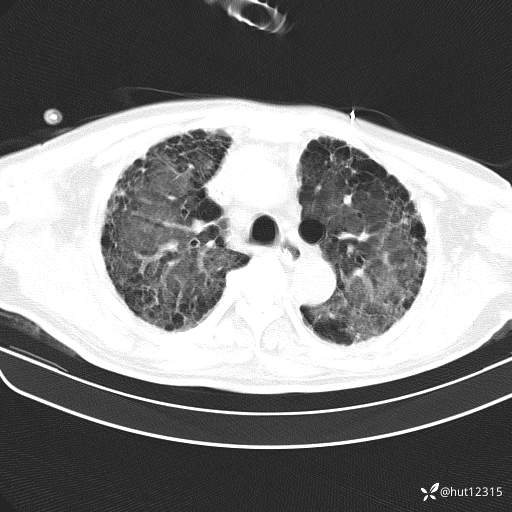

CT:肺纤维化并感染

2.特发性肺纤维化并重症肺炎,ARDS